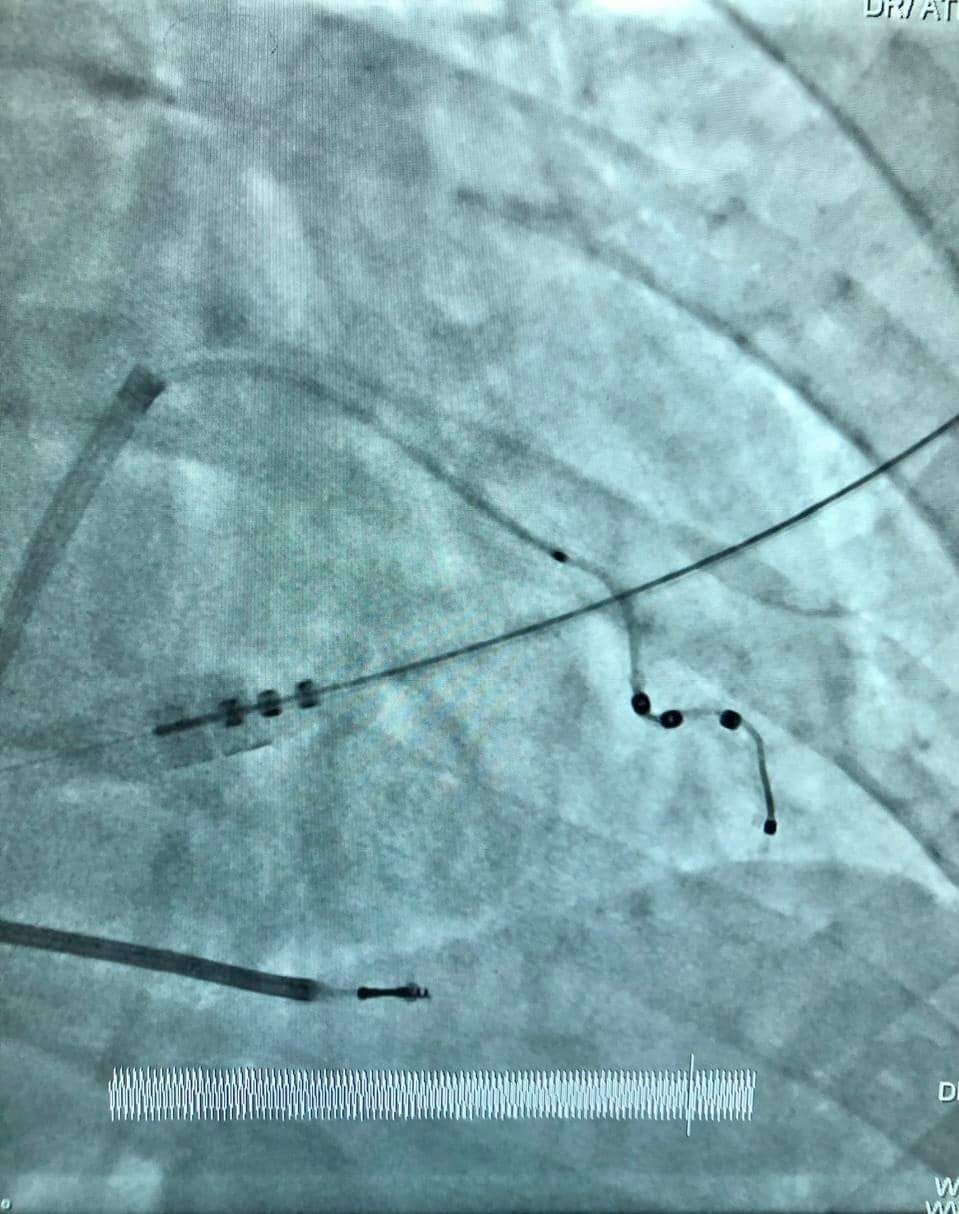

جانب من إجراءات العملية

أثناء إجراء العملية

أعلن مستشفى المنصورة التخصصي التابع لأمانة المراكز الطبية المتخصصة عن زراعة وتركيب جهاز منظم ثلاثي دائم بصاعق داخلى لأول مرة بقسم القسطرة التداخلية بالمستشفى، حيث قام فريق طبى بقيادة الدكتور هانى عبد الشكور بزرع جهاز CRT - D لمريض يبلغ من العمر 68 عاما، ويعاني من ضعف شديد بعضلة القلب، وتعرض مرات متعددة لخلل فى كهرباء القلب فى شكل تسارع وارتجاف بطينى، وهى حالة عالية الخطورة، ومهددة للحياة.

يساعد هذا الجهاز حجرات القلب على الانقباض بطريقة أكثر تنظيمًا وكفاءة، وهو خيار علاجي لمرضى اعتلال عضلة القلب التوسعي، ورغم الصعوبات الفنية الكبيرة، وخطورة الحالة، تم الإجراء الطبي بنجاح كبير، وتحسنت حالة المريض بشكل كبير.